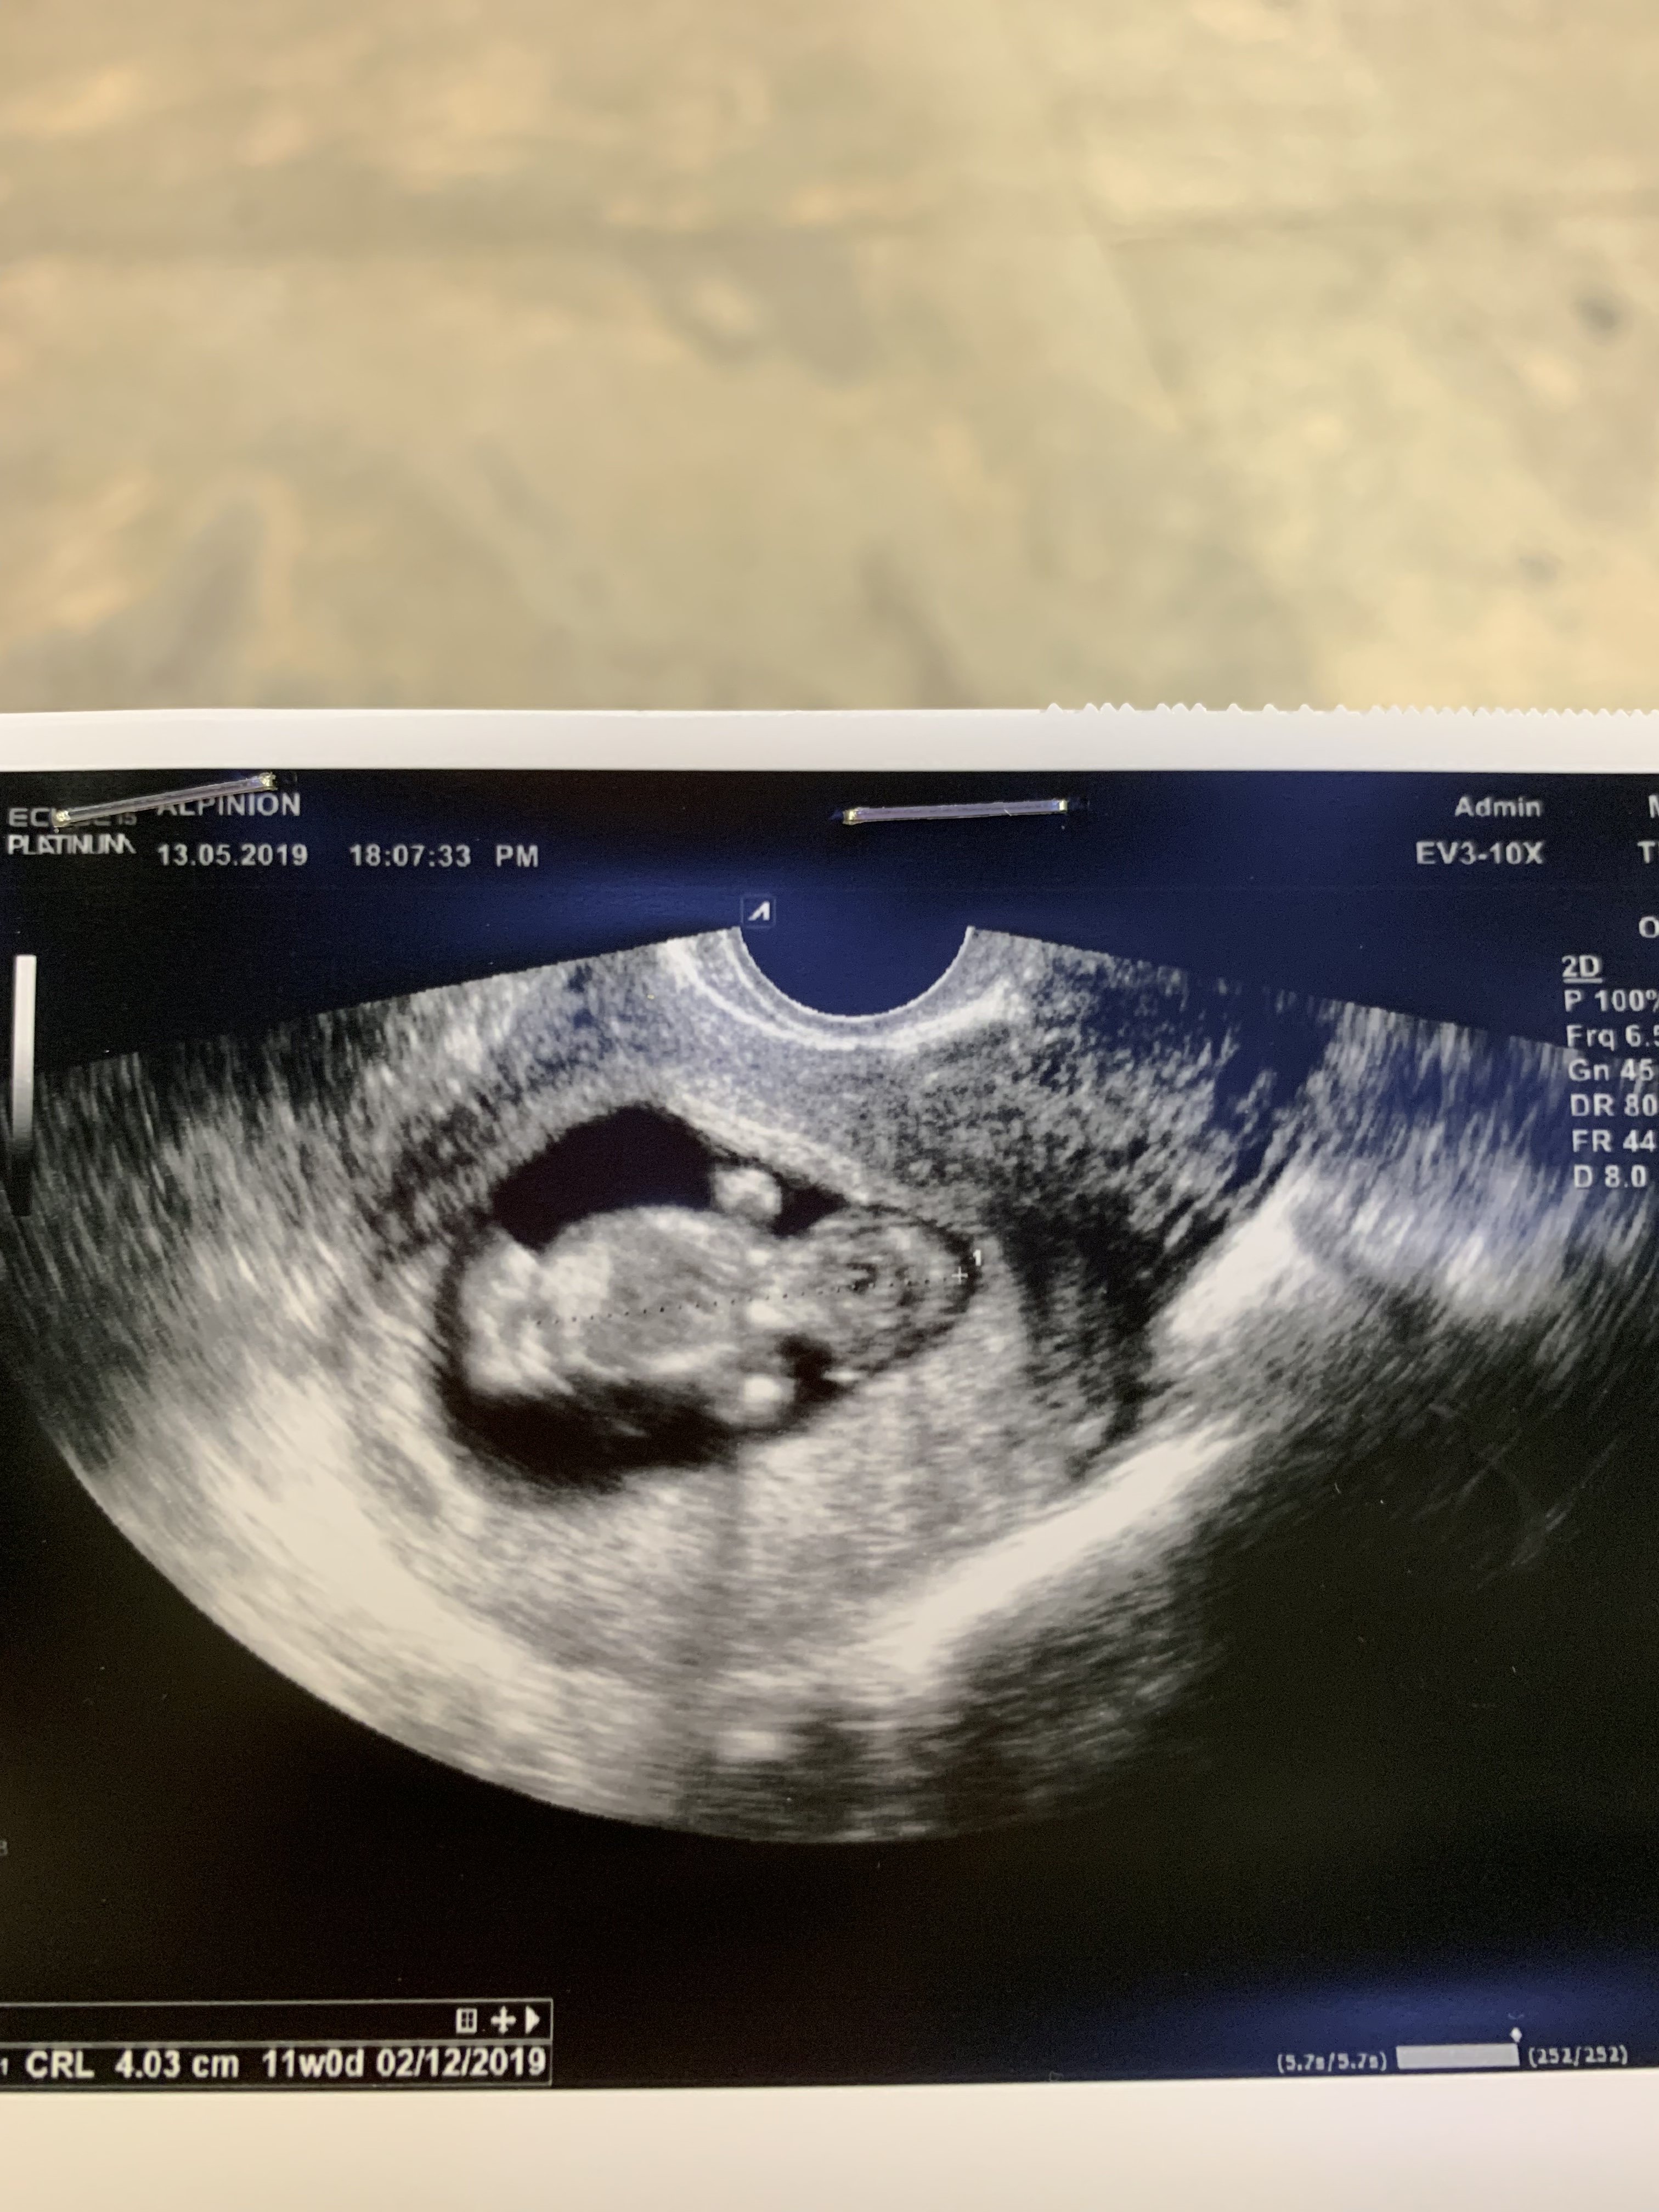

U mnie też ktoś taki zamieszkał - 4 cm. Usg z wczoraj:

Zobacz załącznik 972436